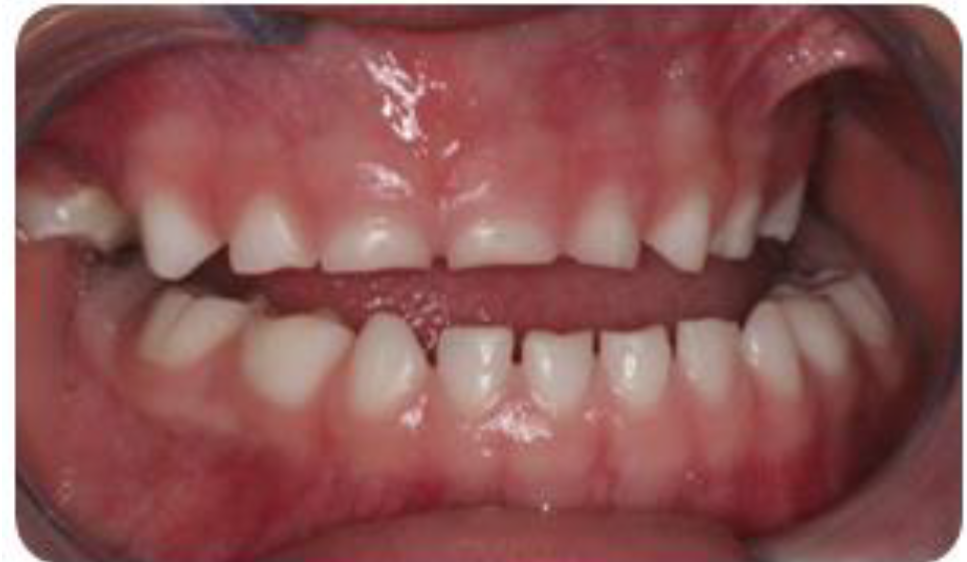

Dentro de las señales clínicas están relacionadas con asimetrías faciales, debilidad labial, respiración bucal, lesiones en la mucosa bucal, denticiones en el borde lateral de la lengua, mordida cruzada anterior y posterior, desgastes de las estructuras de soporte de los dientes, (desgastes lisos, rechinamiento y desgastes rugosos, apretamiento), ensanchamiento de la lamina dura, fracturas dentarias o de restauraciones, incremento de la línea alba, formación de trincas o facetas en los dientes, erosiones cervicales en los dientes, problemas periodontales, mobilidad dentaria, desarrollo de una falsa clase III, aceleración del proceso de rizólisis en dientes deciduos, alteración en la cronología de erupción de dientes permanentes y apiñamiento dental. Por otro lado, en relación a los síntomas relacionados al bruxismo se encuentran: hipersensibilidad pulpar, dolores de cabeza, hipertrofia y dolor a la palpación de los músculos masticadores (masetero, temporal y pterigoideo lateral), dolores y disturbios en la ATM, dolores al abrir o masticar.

Evaluación de los movimientos mandibulares, con presencia de desvió de línea media, con abertura máxima de 43 mm y lateralidad izquierda de 7 mm, sin presencia de overjet u overbite.

En la evaluación dentaria, se observa ausencia de la pieza 54, sin presencia de overjet y overbite, con clase I molar y caninos y desvío de línea media.

Al hablar de la Incidencia de bruxismo en niños, Serra-Negra (Serra-Negra, et al., 2009) no encontró relación de la edad con el bruxismo. Por otro lado, Guoa (Guo, et al., 2018) encontró que las edades entre 5 a 7 y de 11 a 12 son edades con factor de riesgo relacionado con el bruxismo, y en este caso clínico, la paciente tiene 5 años, por lo cual está dentro de las edades que Nascimento & Silva (2018) mencionan como edades más predisponentes.